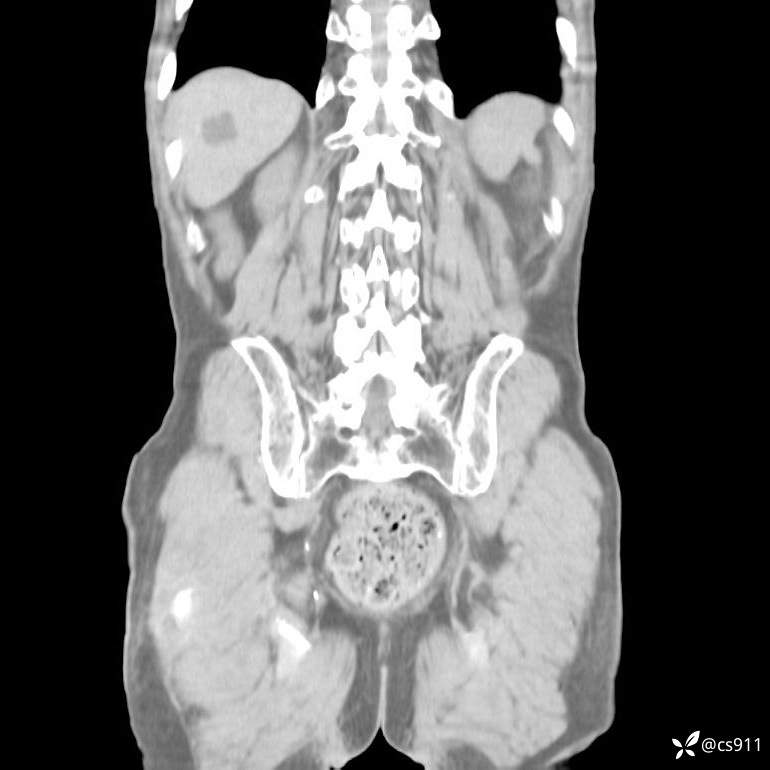

急腹症之急诊CT,原因?答案公布

男,77岁,腹痛、腹胀伴恶心呕吐1天。呕吐胃内容物,非喷射性呕吐,有咖啡色样胃内容物,诉有胃穿孔病史。查体:全腹平,下腹部压痛,全腹无反跳痛,叩诊呈浊音,移动性浊音阴性,肠鸣音减弱,1-2次/分。肛检:直肠未扪及明显肿物,可触及大量粪块。

T 36.6℃ P 80次/分 R 26次/分 BP 100/60mmHg

白细胞(WBC) H 14.55 10e9/L 4-10

红细胞(RBC) 4.58 10e12/L 4.3-5.8

中性粒细胞百分率(NEUT%) H 85.7 % 40-75

血淀粉酶(AMY) HH 1859 U/L 35-135

癌胚抗原(CEA) H 27.44 ng/ml 0-5

呕吐物 潜血试验 * 阳性 阴性

患者轮椅入室检查神志清楚, 能配合摆位和呼吸